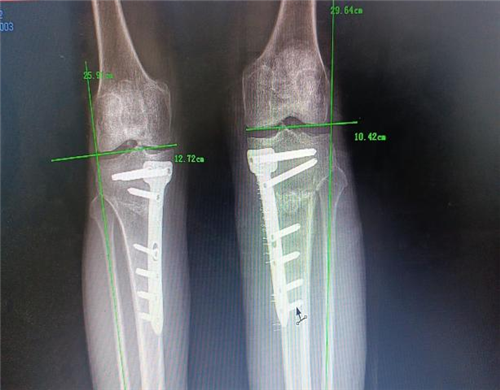

手术如期进行,在骨科手术机器人“透视眼”和“稳定手”的精准操作下,患者术中测量内翻畸形纠正,胫骨近端后倾角92°。术后,患者左膝疼痛明显缓解,关节活动度较术前明显改善,术后3天即扶拐下地行走,4周后即可完全负重。